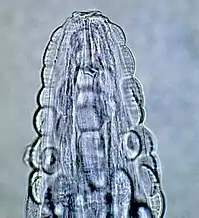

![]() Самець Gongylonema pulchrum | ||||||||||||||

Збудник — нематода Gongilonema pulchrum. Самець завдовжки 47–62 мм, завширшки 0,17–0,195 мм; самка завдовжки 120—145 мм, завширшки 0,350 мм.